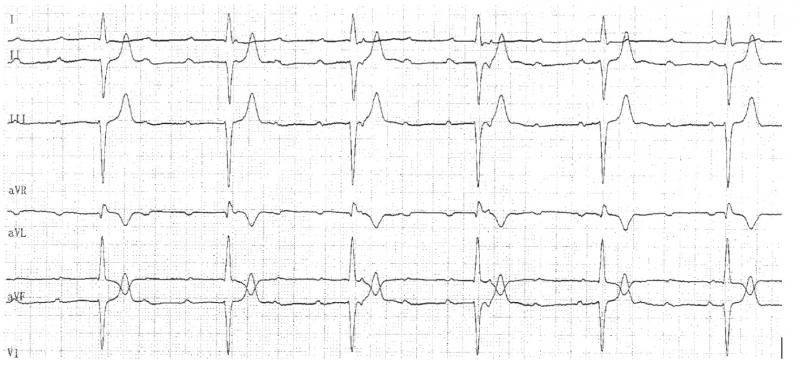

Fig 21 : Dissociation AV complète. C’est un BAV du 3ème degré.A) L’échappement est haut situé car les QRS d’échappement sont fins. B) L’échappement est bas situé car le QRS est large.

B

Fig 22 : On peut mourir d’un BAV complet. Soit par bradycardie excessive A, soit par torsade de pointe liée à la bradycardie B.